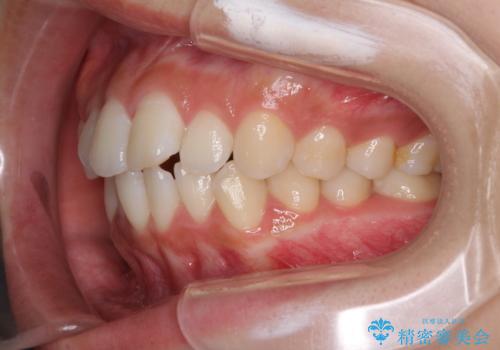

前歯のデコボコと突出感 インビザラインで改善

- 上下前歯のデコボコを気にして来院された患者様です。

インビザラインによる上下歯列の側方拡大と後方移動、IPR(歯と歯の間を削る)にるスペースの獲得により歯列を整えることとしました。

骨格的な左右差があったため、上下の正中を合わせることは困難かと思われましたが、何とか合わせることができました。

一方、骨格の差は改善できないため、奥歯の咬み合わせに物足りなさを感じました。

奥歯の咬み合わせによる不自由はなく、患者様に大変満足していただきました。